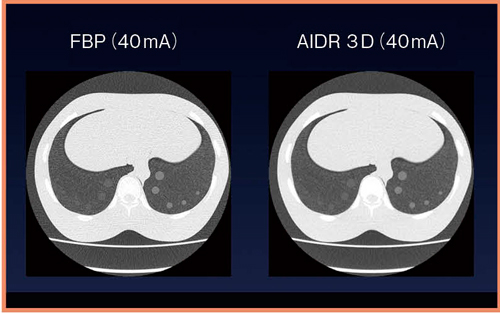

胸部領域におけるAIDR 3Dの有用性について,ファントム実験による視覚的評価を行った。実験では,左肺に結節,右肺にすりガラス状結節のあるファントムを使用した。管電流を270,200,100,60,50,40,30,20,10mA に設定して撮影し,FBP法とAIDR 3Dで比較した結果,FBP法の画像はノイズが多いが,同線量において,また,線量が低くなるにつれてAIDR 3Dにおける結節同定における有用性が高くなり,AIDR 3Dでは低線量下においても評価が可能になる傾向があった。

ファントム実験の統計学的処理を行った結果,270mAで撮影し,FBP法で再構成した場合のAUC(area under the curve)を基準とすると,FBP法では60mA,AIDR 3Dでは40mAまで下げることが可能であった。40mAで撮影したFBP法の画像とAIDR 3Dの画像を比較すると,AIDR 3Dの方が結節が鮮明に描出されている(図2)。

図2 40mAでのFBP法とAIDR 3Dの視覚的評価